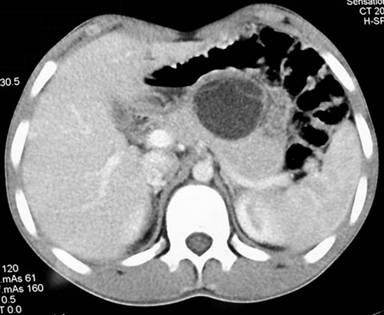

Plain X-ray of the abdomen revealed classical curvilinear calcification in only one patient with a hydatid cyst in the pancreatic body (Figure 1). Ultrasonographic examination which recorded the site, size and extent of the lesions, documented the cystic lesions as anechoic rounded structures in all cases. An abdominal CT scan documented the cysts as spherical hypodense space-occupying lesions. All the lesions were solitary, measuring 26-50 mm in diameter (mean 36.7 mm). Five lesions were cystic with thin walls and one lesion appeared as a multiseptated cyst. Magnetic resonance imaging for defining the lesion and its relationship with the pancreatic duct was performed in three patients (two lesions in the head and one in the body of the pancreas). Two lesions were located in the head (Figure 2, 3, 4, 5), two in the body (Figures 6 and 7) and two in the tail region of the pancreas (Figure 8). In two cases, a preoperative diagnosis was possible due to the presence of classical features which also included a concomitant hydatid cyst in the liver in one patient. All patients underwent surgical exploration; intraoperative cyst puncture for aspiration cytology was successful in three cases (two cases with cysts in the head and one case with a cyst in the body of the pancreas); the results of cytological examination were positive in all cases. A fragmented laminated membrane was observed in two patients, scoliosis in three and hooklets in one patient (Figure 9). The laminated membrane was seen as a foliated, acellular, pale, eosinophilic structure which stained strongly positive with periodic acid Schiff staining and negative with alcyan blue staining. The hooklets had a characteristic shape presenting as a blade, a guard and a root. They were not stained with Papanicolaou stains and their appearance was enhanced by turning down the microscope condenser. There were no complications after diagnostic aspiration. In all three cases, the aspirated fluid was colorless and contained a mean sodium level of 128 mEq/L (range: 128-130 mEq/L), chloride level of 69 mEq/L (range: 65-70 mEq/L) and potassium level of 5.8 mEq/L (range: 5.4-6.3 mEq/L). Cysts in the distal pancreas observed in the two patients were treated by a distal pancreatectomy with splenectomy. Cysts in the body were treated by a pericystectomy in one patient (Figure 10) and a central pancreatectomy in another patient. Cysts in the head region in two patients were treated with evacuation, partial cystectomy and tube drainage of the cavity after protecting the surgical area with a scolicidal solution (Figure 11). Both patients underwent T-tube drainage of the common bile duct; there was rapid regression of the jaundice in these patients. The T-tube cholangiogram confirmed the free flow of bile into the duodenum; the tubes were eventually removed in the third postoperative week. Postoperative confirmation of the hydatid cysts was obtained on the basis of the histopathological findings. There were no postoperative complications; all patients recovered uneventfully. The antihelminthic drug, albendazole, was administered postoperatively (10 mg/kg body weight/day) in all cases for a period of 6 months. All the patients were followed up at three-month intervals and each patient underwent clinical examination, abdominal ultrasonography and indirect hemagglutination tests; no patient had cyst recurrence or dissemination. The mean follow-up time was 58.7 months (range: 4-120 months).

Figure 4. Contrast-enhanced computed tomography scan of the abdomen demonstrating a solitary cystic lesion (50 mm) in the pancreatic head. Note the distended gall bladder (Patient #6). |

Figure 5. T-weighted magnetic resonance image in the same patient demonstrating high signal intensity due to the cystic lesion in the head of the pancreas with an obstructed biliary ductal system (Patient #6). |